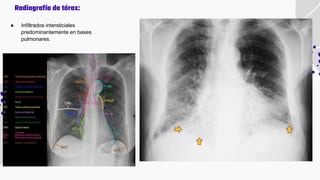

● Infiltrados intersticiales

predominantemente en bases

pulmonares.

Radiografía de tórax:

● Infiltrados intersticiales predominantementeen bases pulmonares. Radiografía de tórax: